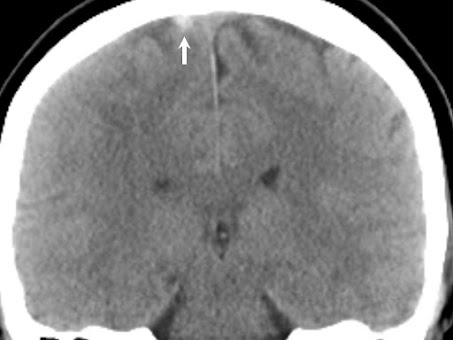

圖一、腦部電腦斷層,見右側皮質靜脈血栓,白色箭頭指的白色圓點處

王小姐打完 AZ 疫苗後第七天開始頭痛、第 13 天開始脖子疼痛,先至外院門診,抽血發現 D-D 雙合試驗(D-dimer)顯著升高,高達 27,500.8 ng/mL,正常值應小於 500 ng/mL、且血小板數值下降,為 77 x 103/µL,正常值應在 130 至 400 x 103 /µL 間,服用頭痛藥物後症狀無緩解,於四天後因左手遲鈍,來到本院急診,急診室的麒亘學長馬上就想到腦靜脈栓塞,緊急安排了腦部電腦斷層,見到右腦頂葉皮質靜脈血栓,併有腦組織腫脹,立刻聯絡神經內科醫師,神經內科柏妤醫師也隨即安排緊急處理,加做打顯影劑的核磁共振,評估是否要緊急取栓,完成後立刻打給我,討論後將她收治加護病房,並於七小時又55分後開始施打免疫球蛋白,住院後頭痛漸改善,抽血亦發現 D-D 雙合試驗指數顯著下降、血小板數值穩定上升,住院 33 天後出院,出院時僅左手略為遲鈍,及偶爾發生頭痛。